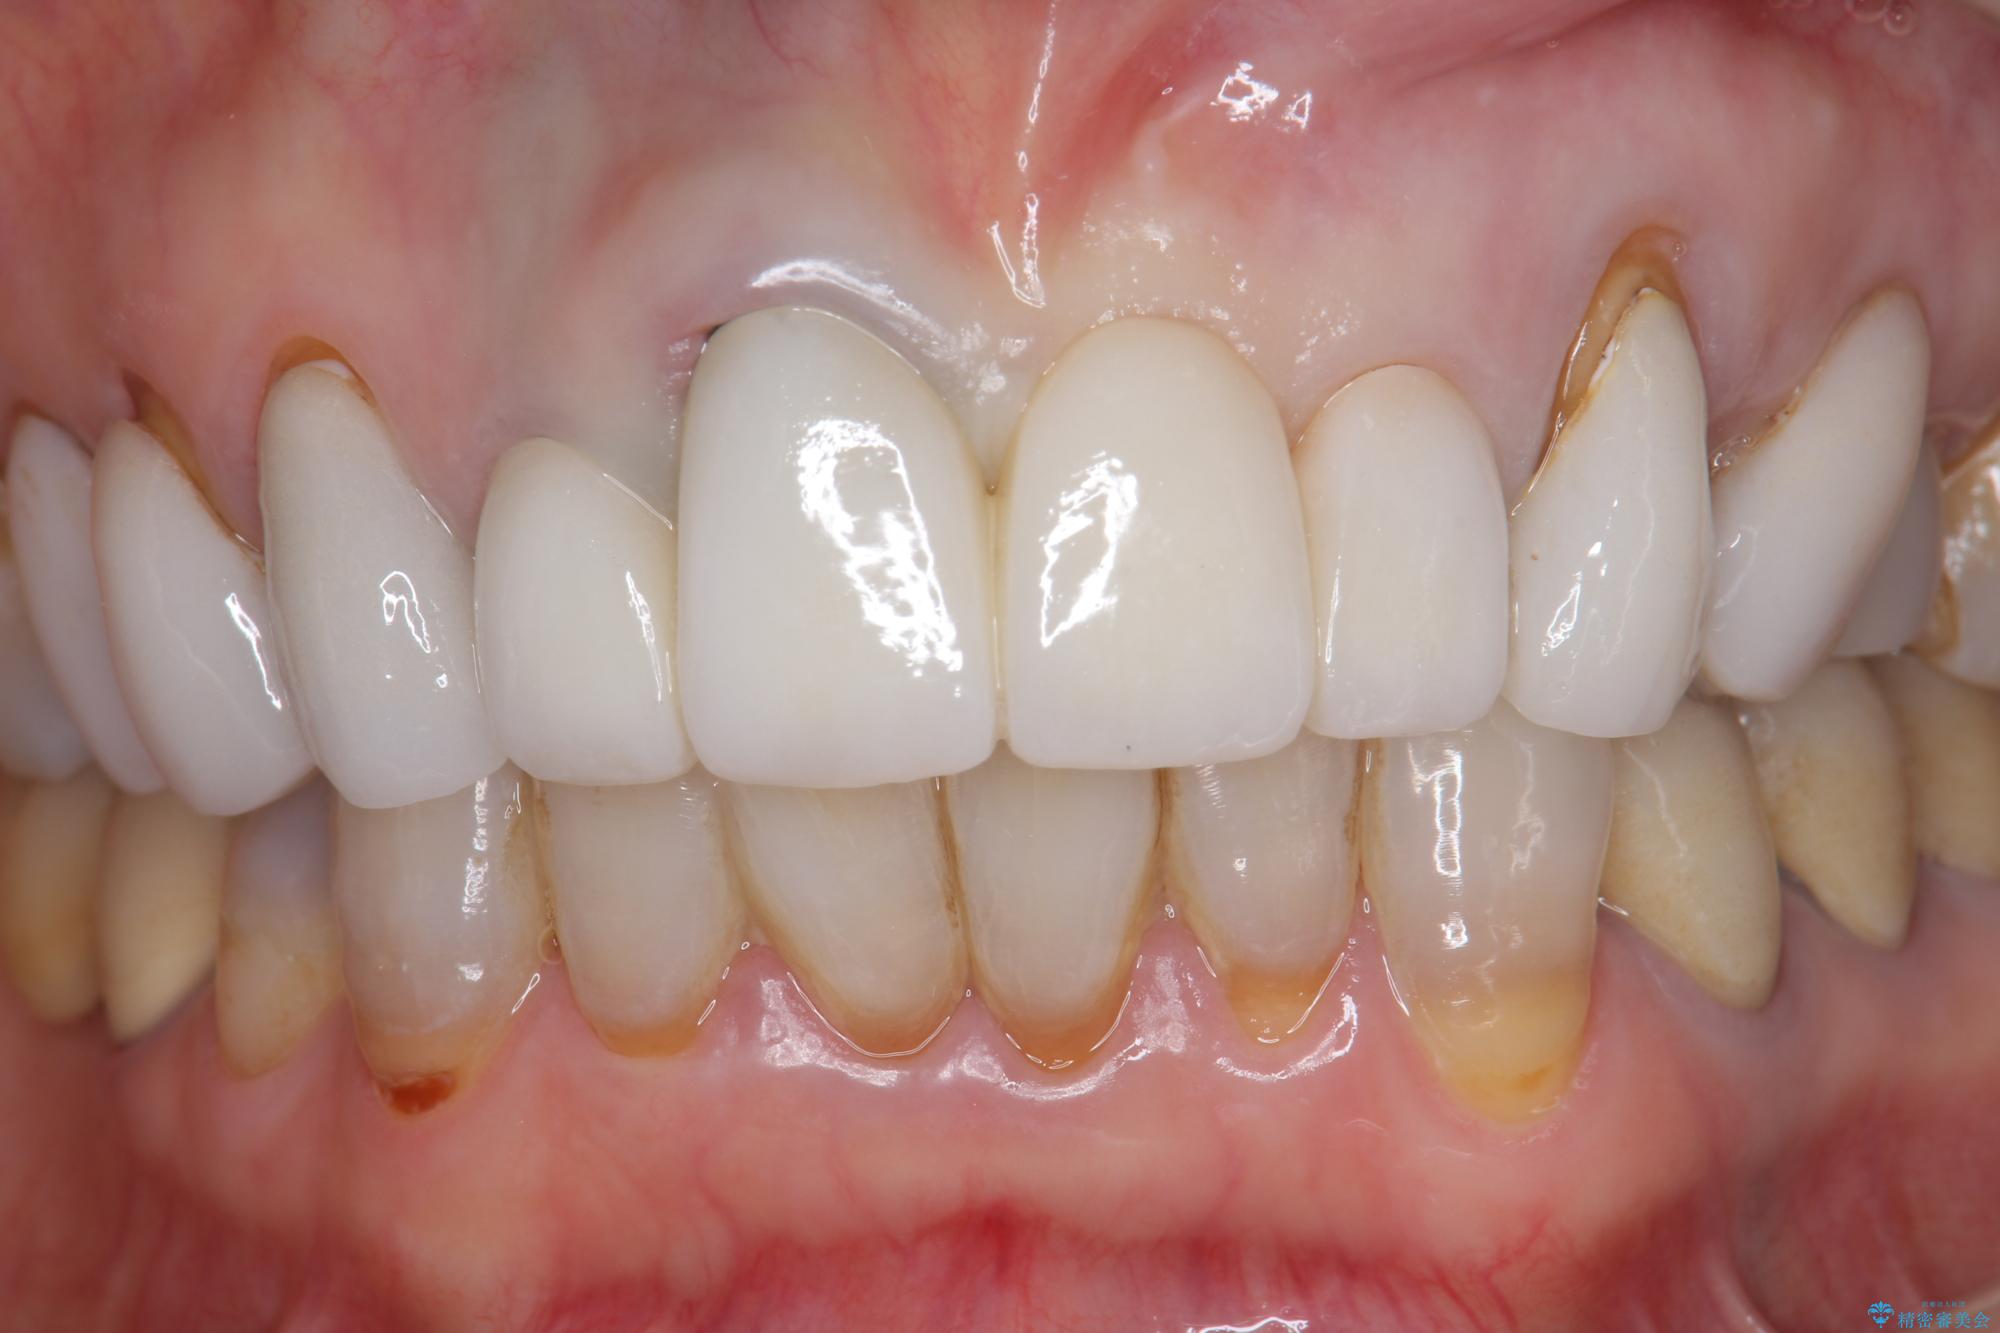

[ セラミック治療 ] 歯ぐきの際の黒ずみを改善したい

- 歯ぐきとセラミックの間の黒ずみが目立つので、きれいに治してほしい。と希望され来院されました。

歯ぐきの位置が変化しクラウン下の歯が見えるようになってしまったことで、審美障害が生じている状態です。

クラウンマージンの再設定を行うことで、黒ずんだ部分を再度覆い、審美障害を改善します。

- 52.8万円(ジルコニアクラウン×4・仮歯×4)費用は治療当時の料金となります